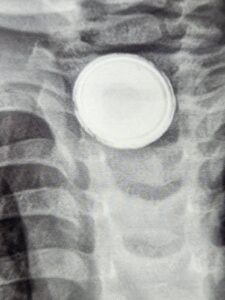

وصل الصغير إلى المستشفى وهو يعاني من صعوبة في البلع وألم شديد، وبعد الفحوصات الطبية والأشعة، تبين وجود «بطارية صغيرة» مستقرة في المريء، مما شكل خطرًا كبيرًا على صحته، نظرًا لإمكانية تسرب المواد الكيميائية منها وتأثيرها السلبي على الأنسجة المحيطة.

وأكد الفريق الطبي أنه تم التدخل الجراحي العاجل باستخدام المنظار الجراحي، حيث نجح الفريق الطبي في استخراج البطارية بأمان، دون حدوث مضاعفات خطيرة، مما ساهم في إنقاذ حياة الصغير وتجنب أي أضرار دائمة.